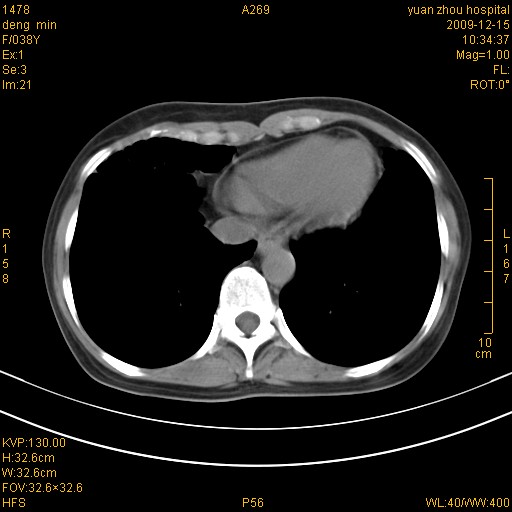

标题: CT23919:F38Y 咳嗽月余 [打印本页]

标题: CT23919:F38Y 咳嗽月余

右肺中下叶、左肺上叶舌段及左肺下叶支气管扩张合并感染。